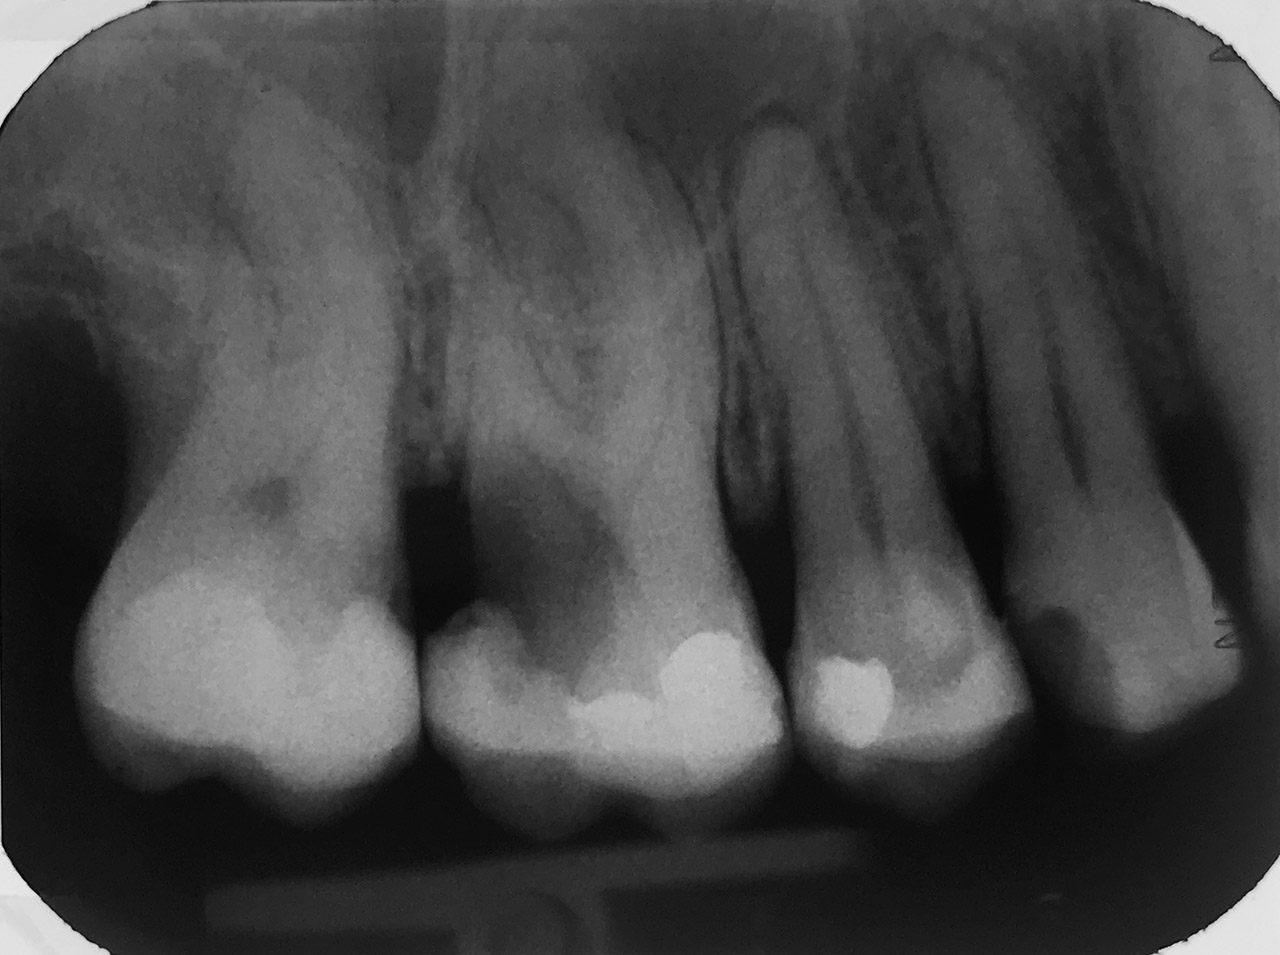

Endodontie/Wurzelbehandlung:

Befund: Aufbißschmerz und Schwellung auf Zahn 46. Frisch zementierte Krone (alio loco).

Therapie: Abnahme der Krone, Entfernung der Zementreste, Revision der insuffizienten Wurzelbehandlung.

Glasfaserstifte und neue Krone, beides adhäsiv zementiert.